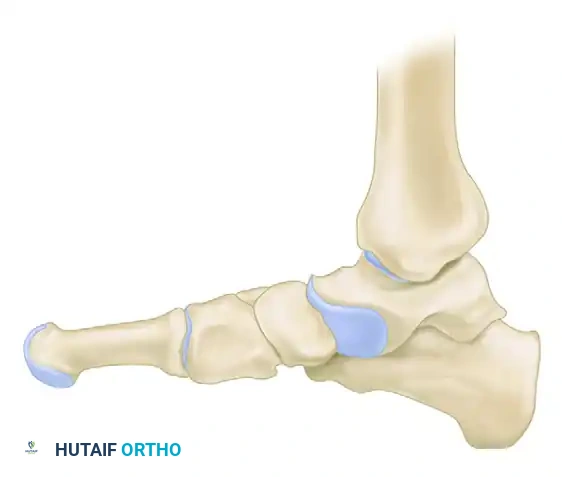

The fundamental goal of the Cotton osteotomy is to restore the tripod effect of the foot—specifically, the weight-bearing distribution between the calcaneal tuberosity, the fifth metatarsal head, and the first metatarsal head.

By plantarflexing the medial column through the medial cuneiform, the surgeon effectively re-establishes the medial pillar of this triangle, ensuring a plantigrade foot following hindfoot correction.